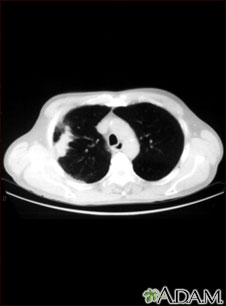

This CT scan shows a cross section of the lungs of a person with lung cancer. The two dark areas in the middle of the screen are the lungs. The light areas in the right lung (on the left of the screen) represent the cancer.